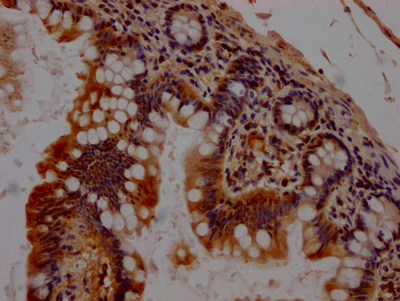

IHC image of CSB-RA176809A0HU diluted at 1:100 and staining in paraffin-embedded human small intestine tissue performed on a Leica BondTM system. After dewaxing and hydration, antigen retrieval was mediated by high pressure in a citrate buffer (pH 6.0). Section was blocked with 10% normal goat serum 30min at RT. Then primary antibody (1% BSA) was incubated at 4℃ overnight. The primary is detected by a Goat anti-rabbit IgG polymer labeled by HRP and visualized using 0.05% DAB.